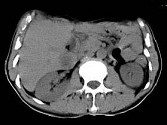

- 单项选择题根据所提供的图像,最可能的诊断是 ( )

A、转移癌

B、肝细胞癌

C、肝脓肿

D、肝血管瘤

E、以上都不是